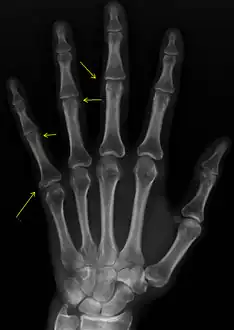

CREST syndrome (calcinosis and sclerodactyly) | |

- X-rays showing calcinosis in a woman with CREST syndrome

- X-ray of subtle calcifications in CREST syndrome